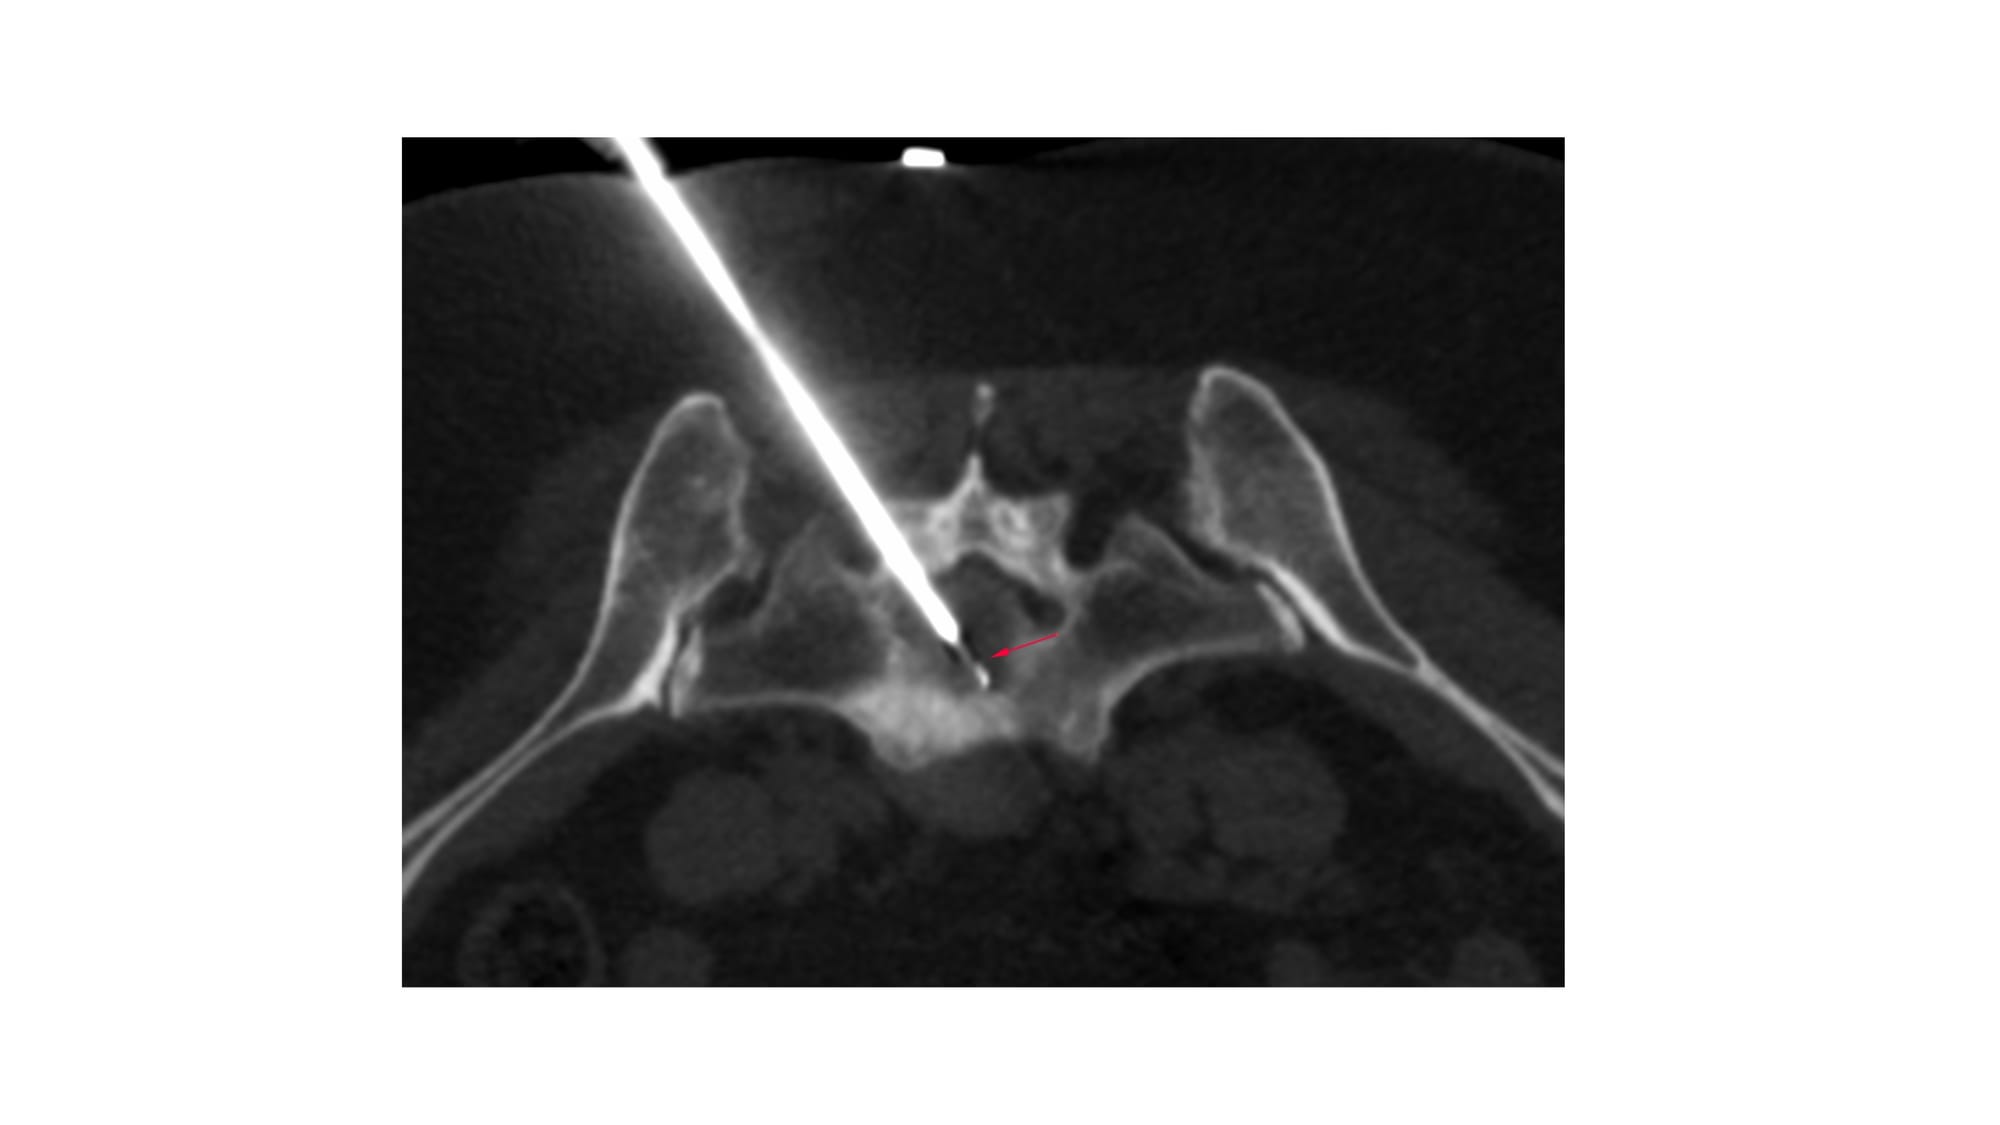

Case of the Day 100 - 2025 09 10 - T2 Dark Thoracic Spinal Vertebral Lesion - Transpedicular Biopsy